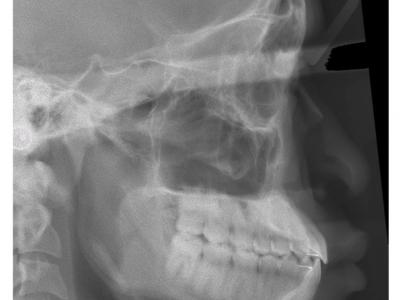

Les deux patients sont classe III squelettique (léger) avec un articulé inversé antérieur, mais avec des rapports de classe I molaire et des diastèmes.

Des dispositifs multi-attaches linguaux ont été choisis pour des raisons esthétiques et pour avoir des torques individualisés.

Le recul des incisives inférieures a permis la correction de l'articulé inversé et repositionné les lèvres (gain esthétique). Les torques ont été bien contrôlés avec des systèmes différents (le premier avec une insertion verticale de l'arc au niveau antérieur et le deuxième avec une insertion horizontale). Le contrôle du torque ne dépend donc pas du type d'insertion, mais du niveau d'insertion de l'arc dans les attaches (insertion au fond pour contrôler) et du jeu de l'arc dans ces dernières.

Dans le deuxième cas, une autre astuce a été de placer des cales indentées sur les molaires pour ouvrir l'occlusion (et donc permettre le passage des incisives inférieures derrières les supérieures), tout en gardant des rapports de classe I latéraux grâce aux indentations (renfort d'ancrage).